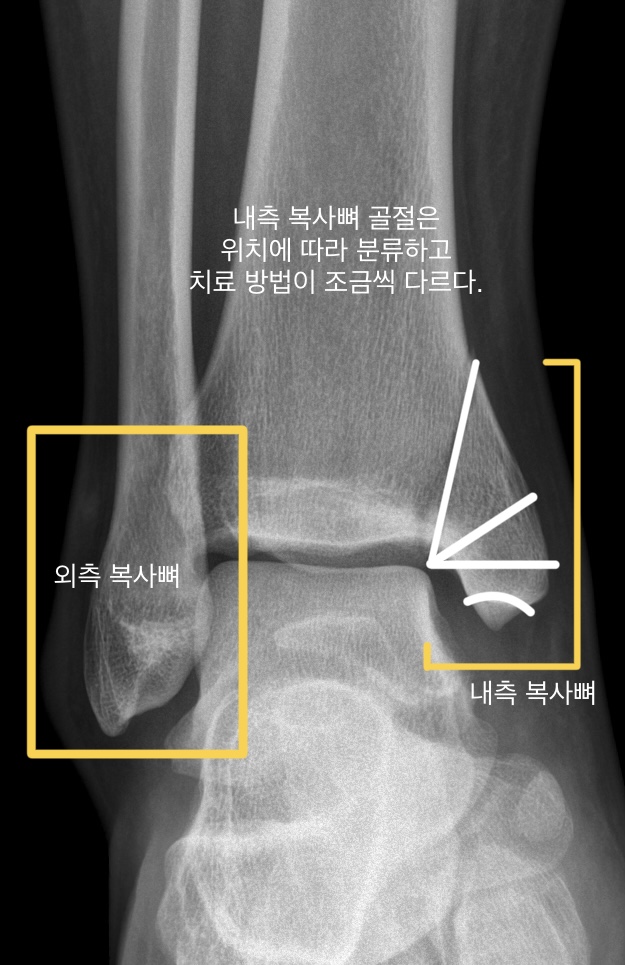

2. 발목 내측 복사뼈 골절의 일반적인 분류

발목 내측 복사뼈 골절은 위치와 골절 정도에 따라 분류할 수 있습니다. 이에 따라 치료 및 예후가 다를 수 있습니다.

- 골절 위치에 따른 분류

견인 골절(avulsion fracture): 인대나 힘줄이 달린 뼈 조각을 떼어 냅니다. 비교적 치료가 간단합니다.

수평골절(horizontal fracture): 골절 부위에 수평 골절이 특징입니다. 수술이나 비수술 치료가 가능합니다.

사선 골절(oblique fracture): 골절이 부분이 사선으로 일어납니다. 이 경우는 주로 비수술 치료가 이루어집니다.

수직 골절(vertical fracture): 골절이 수직 방향으로 발생합니다. 이는 전단력 때문에 수술 치료가 주로 이루어집니다.